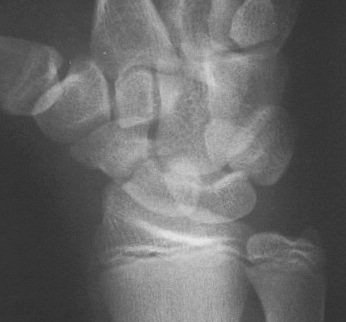

Clinical Example: Scaphoid fracture with total avascular necrosis similar to Preiser's disease

One of the problems with scaphoid fractures is ischemia of the proximal fracture fragment resulting in delayed union, nonunion or irretrievable avascular necrosis. In this case, ischemic changes involving the entire scaphoid are documented following a scaphoid fracture due to minimal trauma. This progressed with cystic changes and AVN on MRI. The patient had persistent pronounced wrist stiffness and pain. As pointed out to me by Dr. Lawrence Schneider (thanks!), this is technically not true Preiser's, for the fracture preceded the AVN.